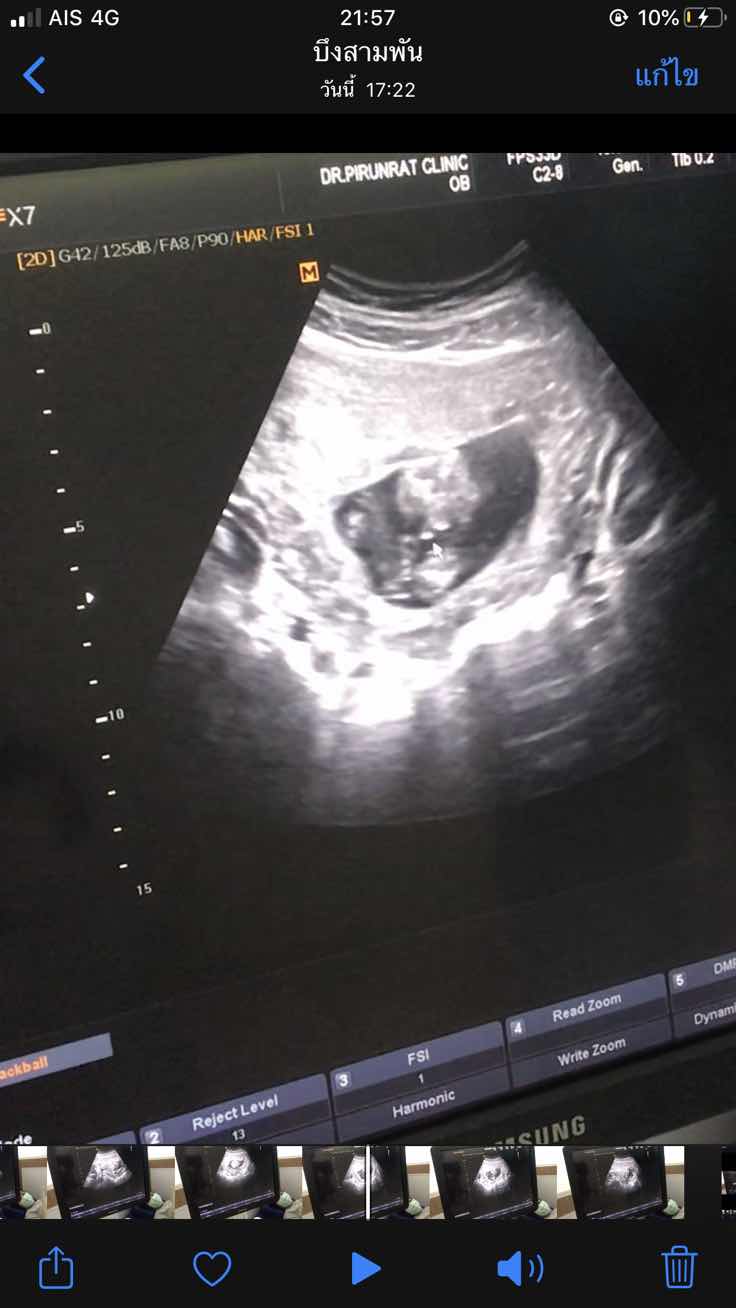

17w+2d เห็นเพศแล้ว